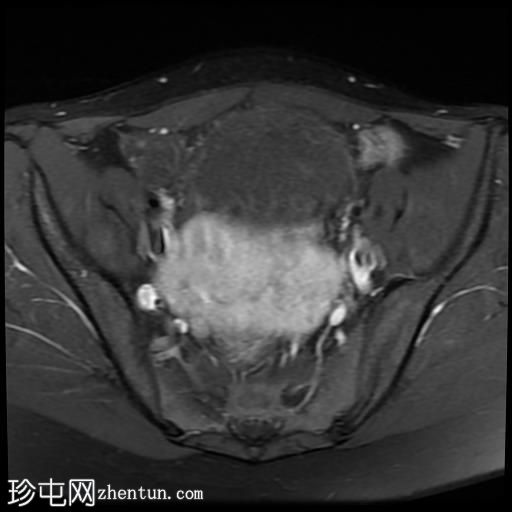

冠状位

T2加权像

盆腔内可见多个边界清晰的肿块:

其中一个位于子宫上方,T2加权像呈中等信号,中心区域呈高信号,增强T1脂肪抑制像未见强化。右侧卵巢增大,增厚的血管蒂扭曲,未见强化,轴位和矢状位T2加权像均显示清晰。

另一个位于子宫后窝,T2加权像呈中等信号,增强扫描显示明显强化。

2个月前进行的MRI检查显示双侧卵巢肿块均有强化,右侧卵巢肿块未见扭转。